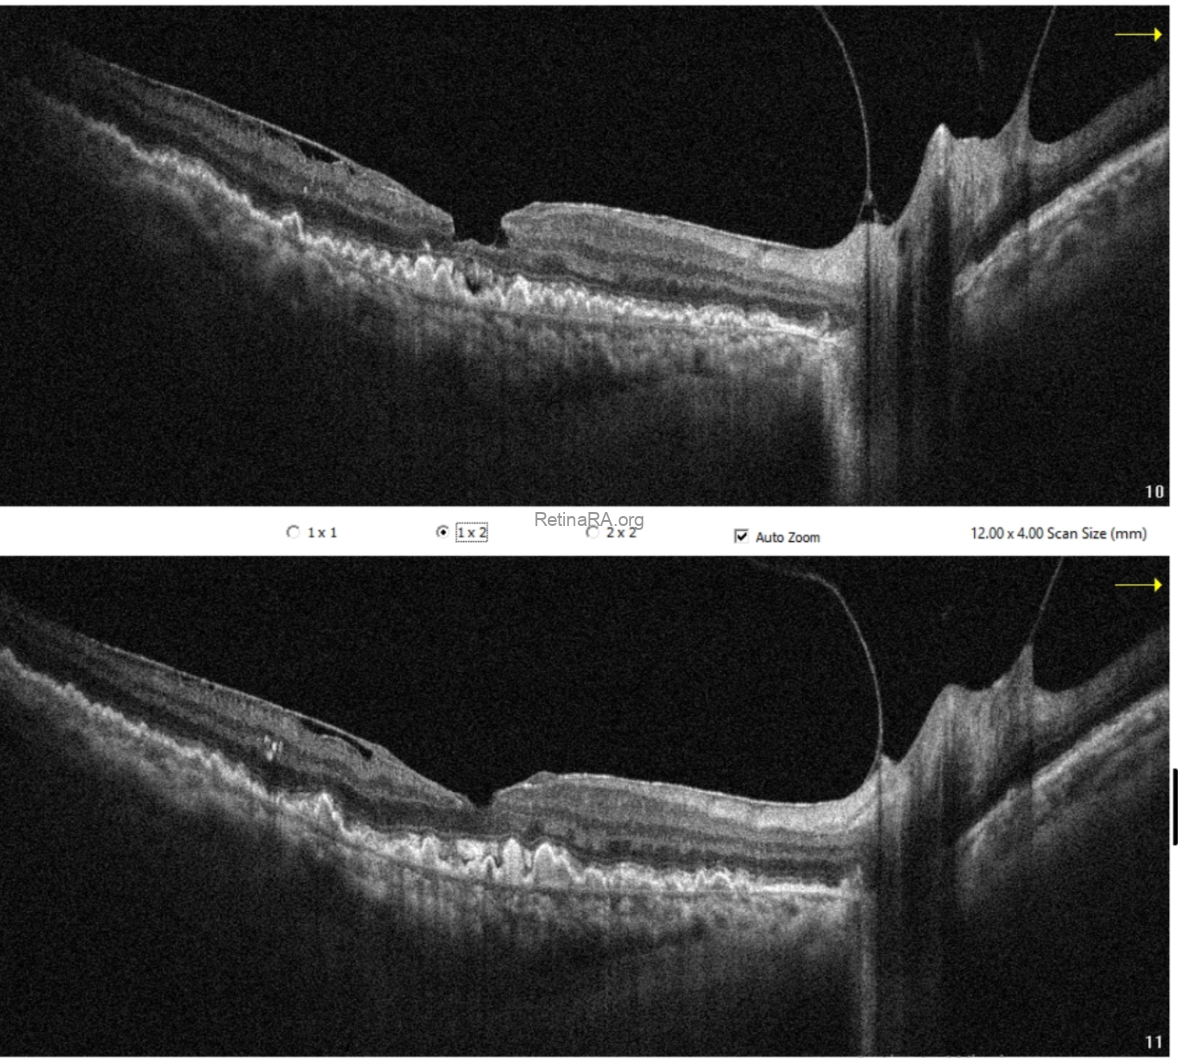

Optical coherence tomography (OCT) demonstrated extensive drusen-like deposits bilaterally, with areas of Bruch’s membrane thickening. In the right eye, there were vitreopapillary traction and an epiretinal membrane associated with a lamellar macular hole configuration, consistent with lamellar hole–associated epiretinal proliferation (LHEP). In the left eye, similarly dense deposits were observed, along with a subtle subfoveal subretinal fluid accumulation. Additionally, there appeared to be localized thickening at the level of the photoreceptor layers.

OCT angiography did not reveal any evidence of choroidal neovascularization. The subretinal fluid was therefore considered likely secondary to retinal pigment epithelium dysfunction.

Taking into account the patient’s systemic history, particularly membranoproliferative glomerulonephritis, these findings are consistent with dense deposit disease. This case highlights that, despite the patient’s advanced age, such presentations should not be attributed solely to age-related macular degeneration. A thorough evaluation of systemic associations is essential for accurate diagnosis.